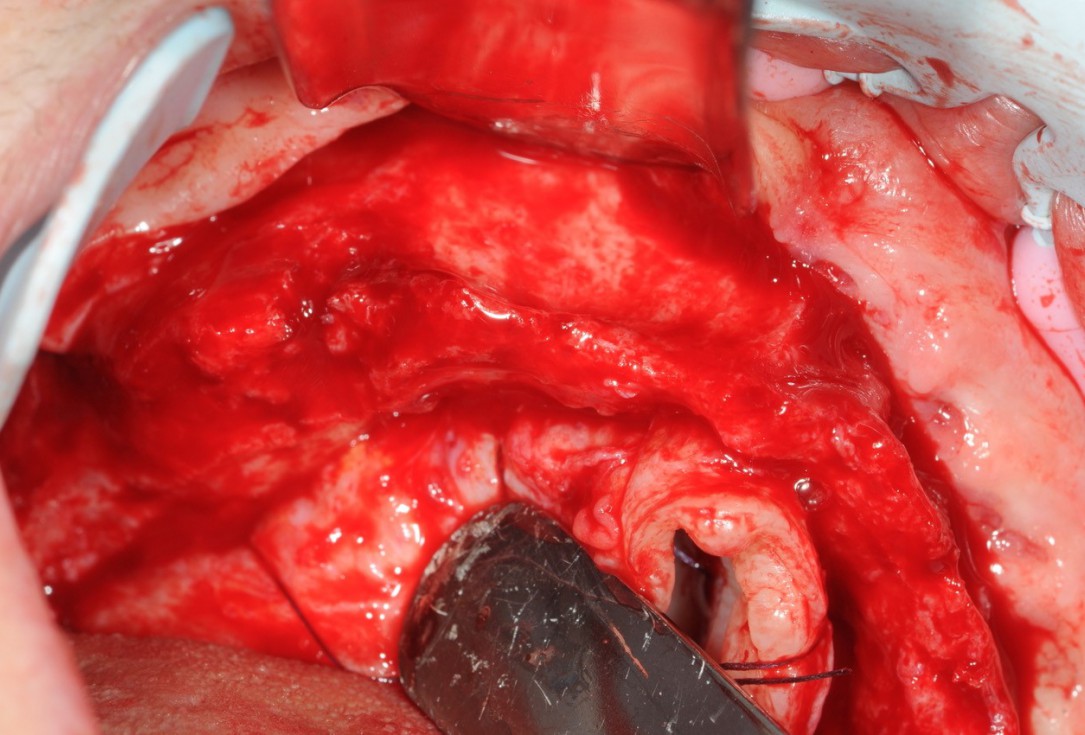

09/21 - Fixation of multiple blocks with osteosynthesis screws

10/21 - Fixation of multiple blocks with screws / crestal view